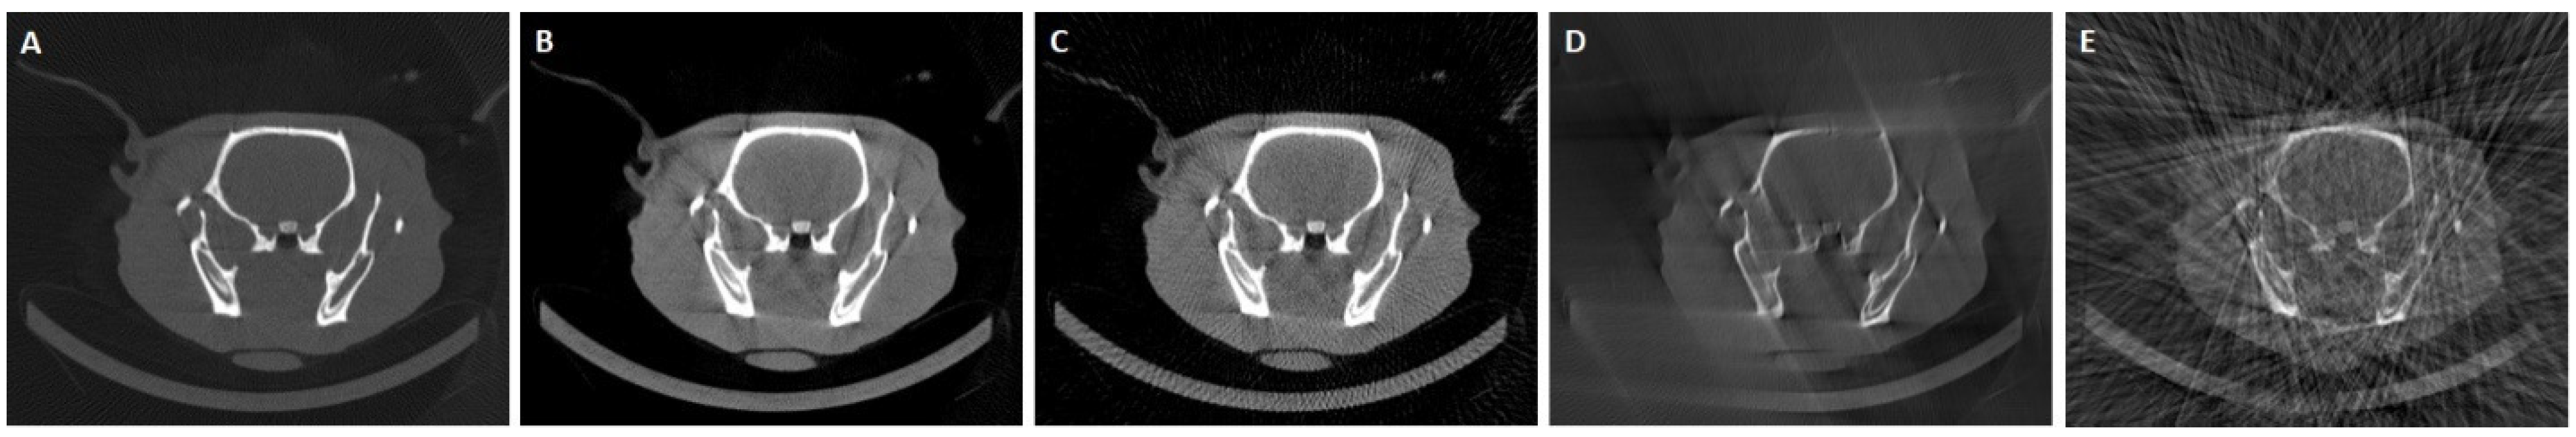

3.3. Results in Conventional Scenarios